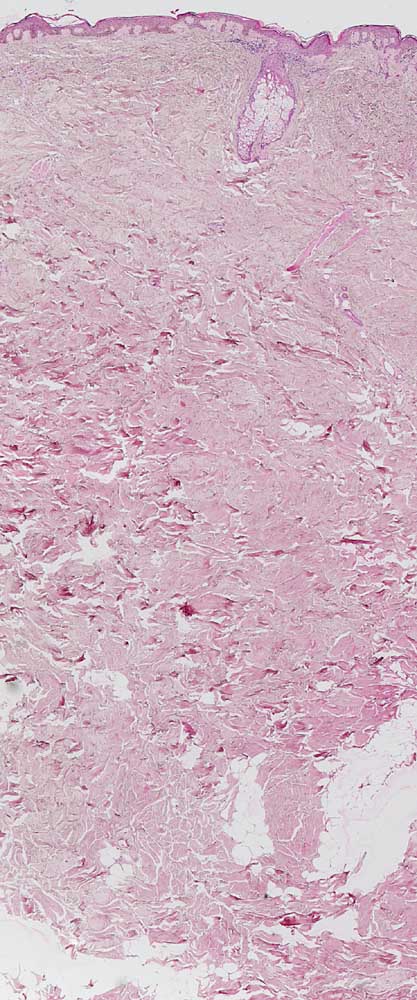

PathoPic ID 7036 - normale Felderhaut vom Rücken

normale Felderhaut vom Rücken

Normalbefund

Haut, Rumpf

Haut

Das Korium der Rückenhaut ist etwas dicker als das Korium der Abdominalhaut. Haare sind nicht sehr zahlreich und reichen nicht sehr tief.

Histologie

25